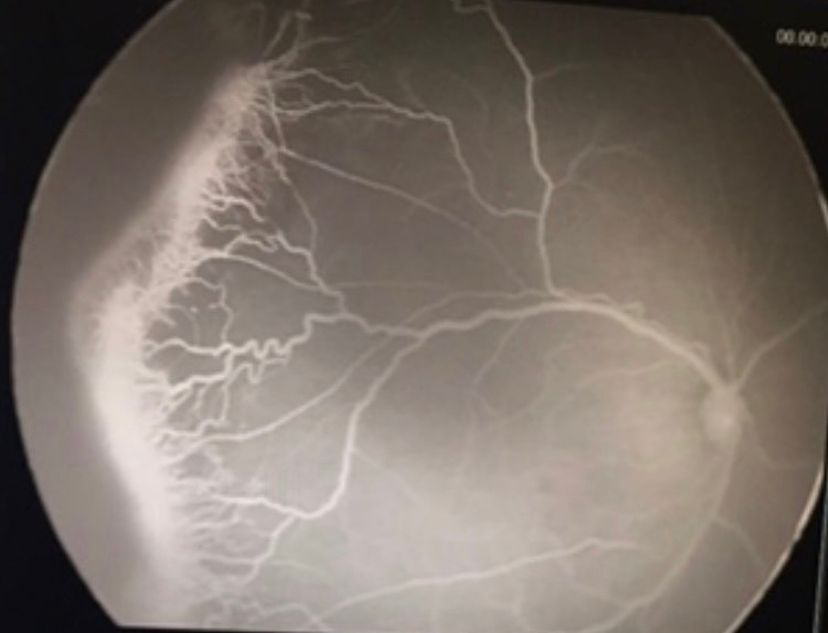

La retinopatía del prematuro (ROP) es una enfermedad que puede afectar a bebés prematuros y que, si no se detecta a tiempo, puede provocar ceguera. Esta condición afecta a la retina, la parte del ojo que detecta la luz y envía señales al cerebro para transformarlas en imágenes y así poder ver, al promover el crecimiento anómalo de vasos sanguíneos que pueden causar desprendimiento de retina y, por lo tanto, pérdida visual irreversible.

En bebés prematuros, los vasos sanguíneos de la retina no se desarrollan por completo. Los siguientes son algunos factores de riesgo de la ROP: